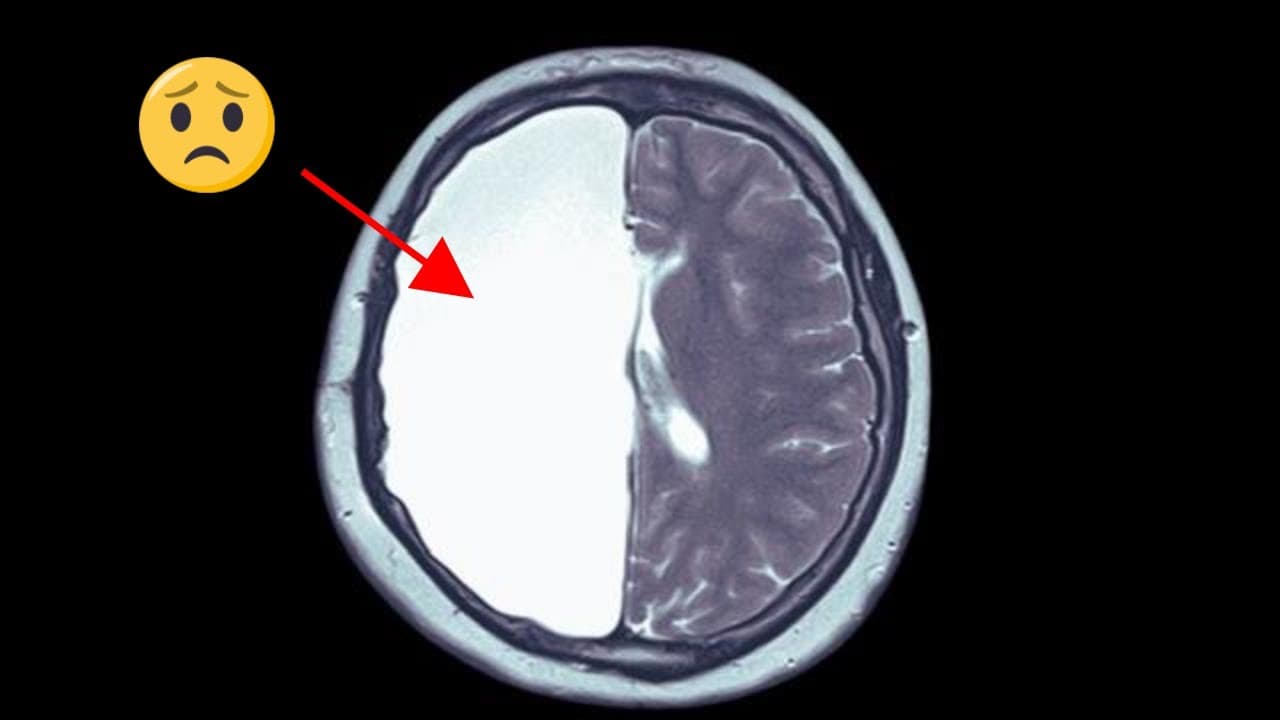

What Happens When We Remove Half of Your Brain? 🧠Neuroplasticity Explained!

In this fascinating video, we delve into the remarkable world of hemispherectomy, a surgical procedure where half of the brain is removed. Join us as we explore the science behind this extraordinary surgery and uncover its surprising implications for human cognition and behavior. @ecgkid #neuroscience #neurology #medicaleducation ____________________________________________________________________ OUTLINE: 0:00 Intro 0:20 Brain Anatomy & Physiology 0:53 Hemispherectomy 1:38 Neuroplasticity 3:2...